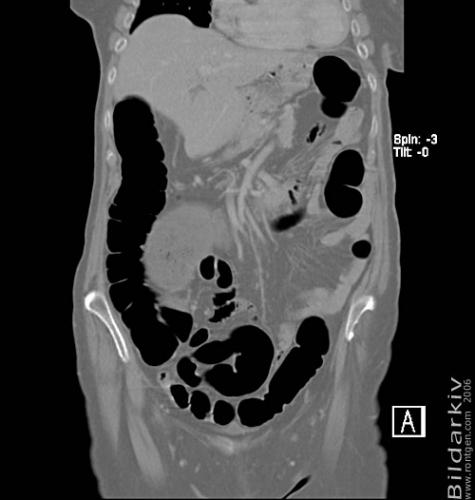

CT colon 20

Datortomografi av tjocktarmen (colon) med infunderad luft i tarmen samt med kontrast i blodbanan. Koronar bildserie.

CT multislice 16